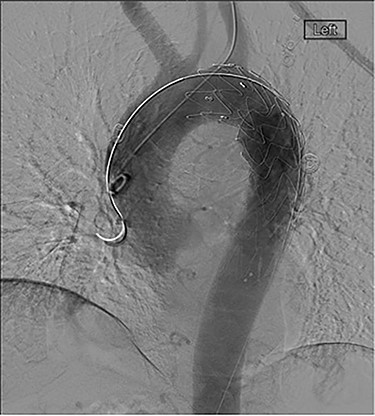

The patient was transferred and stabilized on the critical care unit and discussed with the interventional radiologist. In conjunction with the interventional radiologist and cardiothoracic teams, the patient underwent radiological stenting of the large aneurysm with TEVAR procedure (Figs 2 and 3). Following the procedure, the patient continued to have large volume haematemesis and melaena and underwent repeat oesophago-gastro-duodenoscopy which demonstrated large amount of blood and clot in the distal oesophagus and stomach with continuous brisk active arterial bleeding at approximately 40 cm, which was unsuitable for any endoscopic therapy. Follow-up CT angiography demonstrated satisfactory appearances of the thoracic aortic stent graft with no evidence of endo-leak. The left subclavian artery was well opacified, and the excluded aneurysm sac contained multiple locules of gas suspicious of ongoing fistulous communication with the oesophagus. Following further stabilization, the patient underwent repeat procedure with identification of a tear in the lower third of the oesophagus. The patient was subsequently managed as an oesophageal perforation with no fluid or oral intake and was commenced on peripheral total parenteral nutrition prior to definitive primary repair.

CT scan demonstrating patent stent with no suggestion of endoleak and lack of contrast in aneurysm sac.